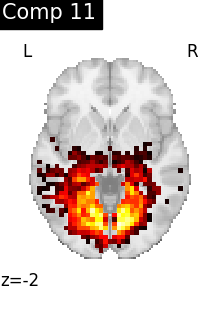

Finally, we plot the map for each ICA component separately

from nilearn.image import iter_img

from nilearn.plotting import plot_stat_map, show

for i, cur_img in enumerate(iter_img(canica_components_img)):

plot_stat_map(

cur_img,

display_mode="z",

title=f"IC {int(i)}",

cut_coords=1,

colorbar=False,

)